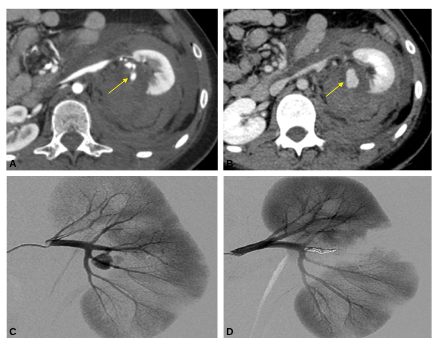

Fig. 39.1. Syndrome hémorragique aigu suite à un coup de couteau dans le dos.

Le scanner après injection met en évidence un volumineux hématome rétropéritonéal, périrénal gauche avec une fuite de produit de contraste dans le hile rénal bien visible au temps artériel (A) et qui se majore au temps parenchymateux (B) (flèches). L’artériographie réalisée en urgence montre la rupture d’un faux anévrisme (C). L’hémorragie est stoppée grâce à l’embolisation de l’artère porteuse avec mise en place de coils (D).

Source : CERF, CNEBMN, 2022.

L’artériographie est réalisée à visée thérapeutique pour faire l’embolisation de l’artère causale. Après ponction d’une artère fémorale le plus souvent, un cathéter est amené par voie endovasculaire jusqu’à l’artère responsable du saignement. Une fois le saignement authentifié par l’injection de produit de contraste qui montre une extravasation (hors du vaisseau) (figure 39.1C), l’artère en cause est occluse par :

- soit le dépôt des spires métalliques (coils) (figure 39.1D).